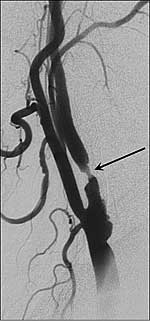

Bildunterschrift: Röntgendarstellung der Halsschlagader. Der Pfeil markiert die Einengung der Halsschlagader durch Plaque (Kalkablagerung).

Bildquelle: Universitätsklinikum Heidelberg